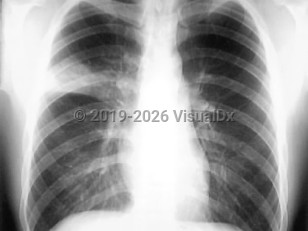

Fever, Cough, 50-59 year old Female

COVID-19